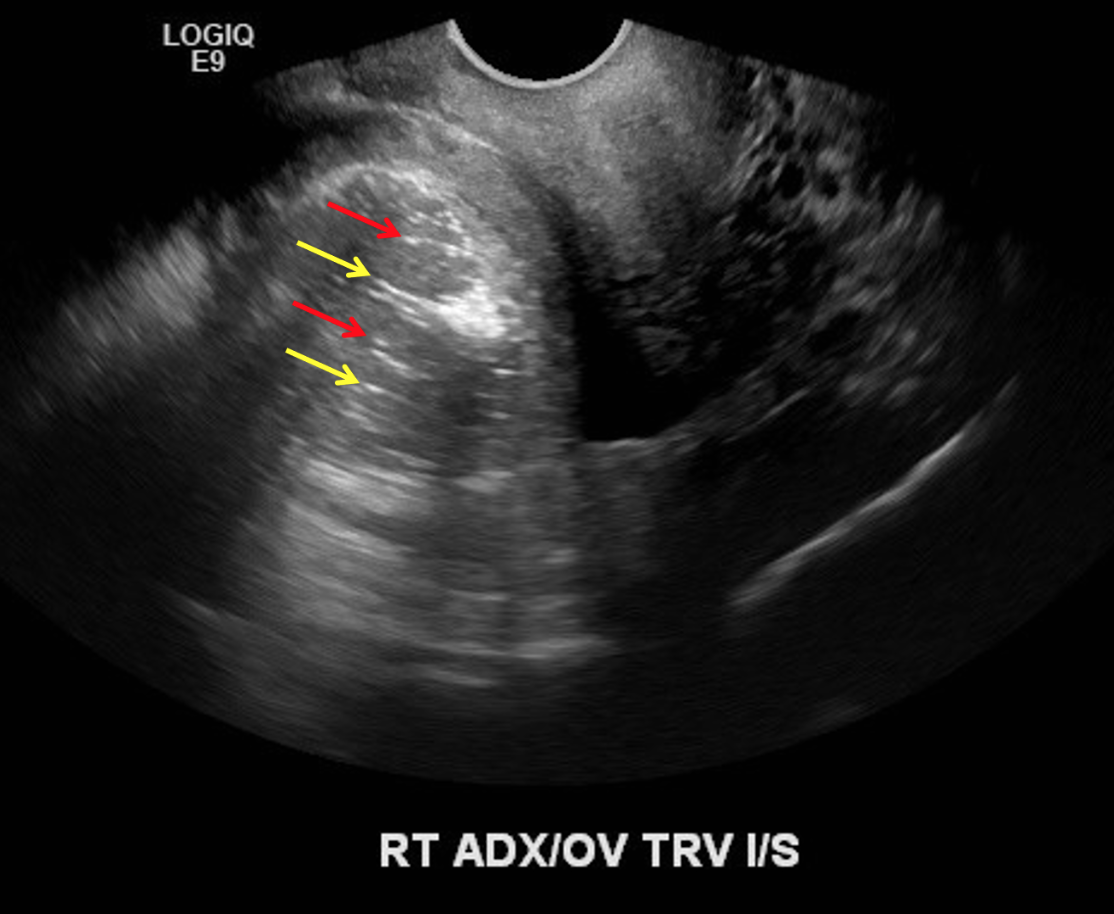

• Dermoid cyst = most common mass to cause

• Look for areas of increased echogenicity = fat

• Look for dot-dash sign = alternating echogenic dots and dashes = represents calcifications and hair

Dot-Dash sign seen with dermoid cysts